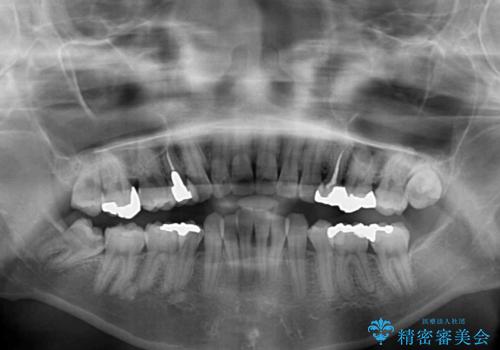

- 抜歯矯正の後戻りで前歯が突出してきていることを気にして来院された患者様です。

口元の突出感を改善するにあたり、抜歯矯正は行うことができないため、奥歯の後方移動とIPR(歯と歯の間を削る)により達成することとしました。

再度後戻りしたときに対応しやすいよう、インビザラインにて矯正治療を行うこととしました。